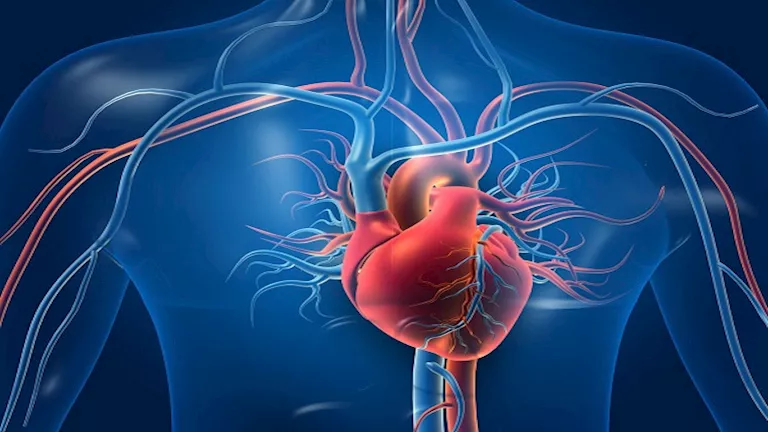

الكثير من الناس يعتقدون أن النوبة القلبية تحدث بشكل مفاجئ، ولكن الحقيقة أن الجسم غالبًا ما يرسل إشارات تحذيرية مبكرة يمكن أن ننقذ بها حياتنا. تجاهل هذه العلامات قد يؤدي إلى مضاعفات خطيرة. من المهم أن نكون على دراية بهذه الإشارات، خاصة تلك التي تظهر على اليدين والأصابع، لأنها قد تكون مفتاحًا لاكتشاف أمراض القلب في مراحلها الأولى. وفقًا لمراكز السيطرة على الأمراض والوقاية منها (CDC)، فإن مرض الشريان التاجي هو أكثر أنواع أمراض القلب شيوعًا، ويؤثر بشكل كبير على تدفق الدم إلى القلب.

ما هي أمراض القلب وأنواعها؟

أمراض القلب ليست مرضًا واحدًا، بل هي مصطلح شامل يضم مجموعة متنوعة من الحالات الصحية التي تؤثر على عضلة القلب والأوعية الدموية. أكثر هذه الحالات شيوعًا هو مرض الشريان التاجي (CAD). يحدث هذا المرض عندما تتراكم الدهون والكوليسترول في الشرايين التاجية، مما يضيقها ويعيق تدفق الدم الغني بالأكسجين إلى القلب. إذا لم يتم اكتشاف وعلاج هذا الانسداد مبكرًا، فقد يؤدي إلى أعراض حادة مثل الذبحة الصدرية أو النوبة القلبية.